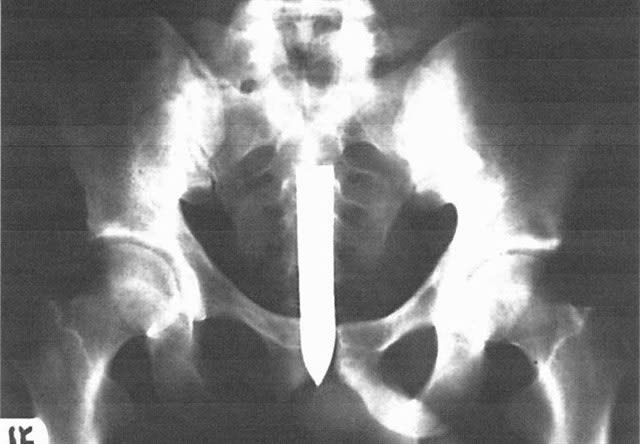

Photo courtesy of Richard Valdemar.